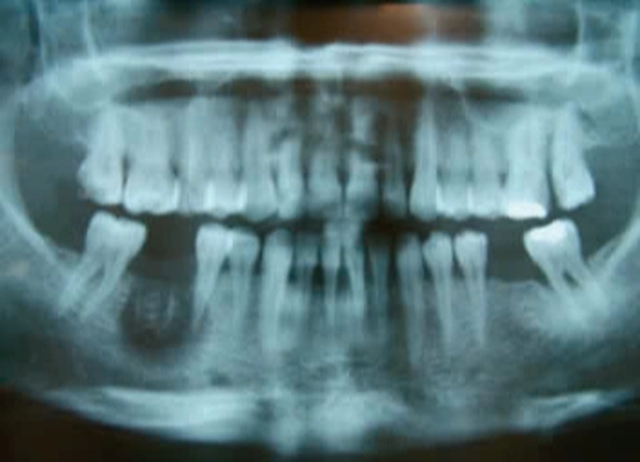

Hoại tử xương hàm ở vị trí răng 46 sau điều trị nội nha có sử dụng thạch tín

Trong nha khoa, việc sử dụng thạch tín có thể gây những biến chứng như: hoại tử xương hàm; hoại tử mô mềm, hoại tử lợi; viêm tủy xương hàm…

GS Ngọc cho biết thêm, trong một đánh giá do Ủy ban Sản phẩm thuốc dùng cho con người (CHMP) thực hiện, các phân tích dữ liệu từ các nghiên cứu trong phòng thí nghiệm và dân số chỉ ra rằng thạch tín có thể gây nguy cơ nhiễm độc gen và có thể làm tăng nguy cơ ung thư. Ngoài ra, đã có một số ít trường hợp thạch tín được cho là đã rò rỉ ra mô nha chu gây hoại tử mô mềm, hoại tử xương hàm.